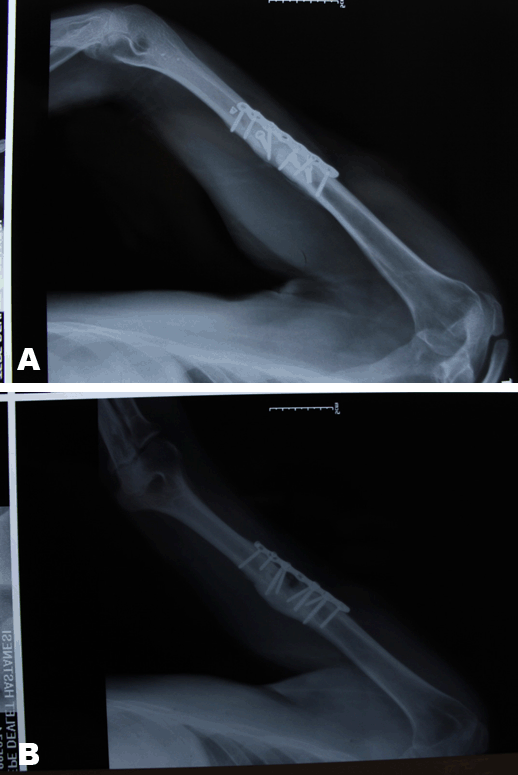

A 28-year-old male diagnosed with closed humerus shaft fracture due traffic accident without neurovascular injury. He was treated with open reduction and plate fixation at another hospital four months ago. (Figure 1A-B) Postoperative period was uneventful. However, there was a lack of union after 12 weeks. (Figure 2) He was presented to our outpatient clinic with severe pain after a minor trauma. The plain radiographs revealed a non-union of humerus shaft fracture with loss of reduction and implant failure with a broken screw. (Figure 3) There was no evidence of infection on clinical examination and C-reactive protein level was also normal. The patient was diagnosed with atrophic non-union with implant failure and offered revision surgery with implant removal, bone grafting and fixation with a longer and thicker plate. However, the patient did not accept revision surgery demanded conservative treatment. Closed manipulation (Figure 4A-B) under sedation and a Sarmiento type brace cast was applied. Although the reduction was good, the patient was informed of high risk of ineffectiveness of this treatment method. During monthly follow-up, there was no loss of reduction again, and at the fourth month follow-up after closed manipulation solid bony union was achieved without any deformity. (Figure 5A-B)

Figure 1: (A, B) Inappropriate plate fixation of humeral diaphysis fracture.

Figure 4: (A, B) Implant after close reduction.